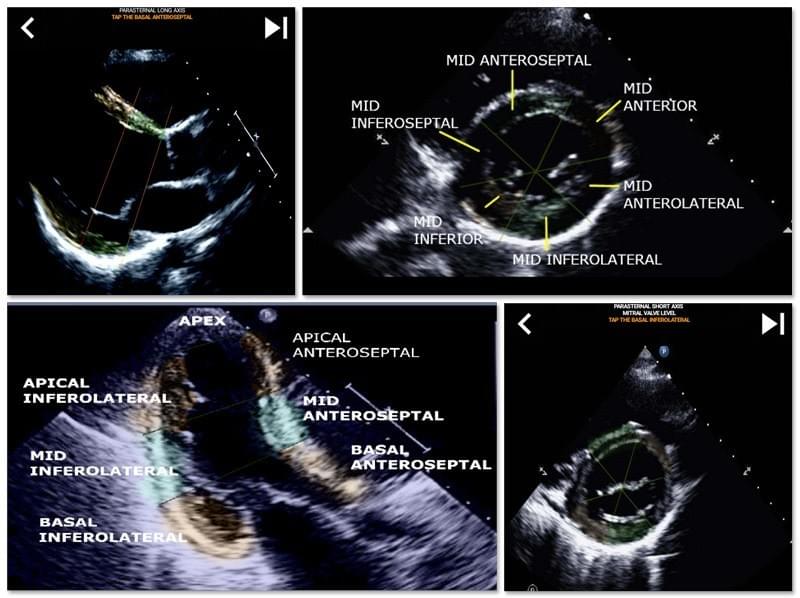

AHA 17 SEGMENT INTERACTIVE HEART QUIZ

It is essential for ultrasound echocardiographers to learn the American Heart Association cardiac segmentation of the left ventricle into 17 segments which is the standard widely used by many other imaging modalities such as magnetic resonance imaging,cardiac nuclear tests, etc... to describe the location of affected segments and function. Many times the person reading your echo will ask " what did you see?" and replying with an exact location of the affected area is what is expected.

This app contains all the echo views showing the AHA segmented myocardium and will quiz you to tap the correct segment. I personally find that repetitive quizzing works best for me when I need to quickly learn/memorize subject. If you are an ultrasound student studying echo/TTE I think this would be an excellent complement to your studies.About Me